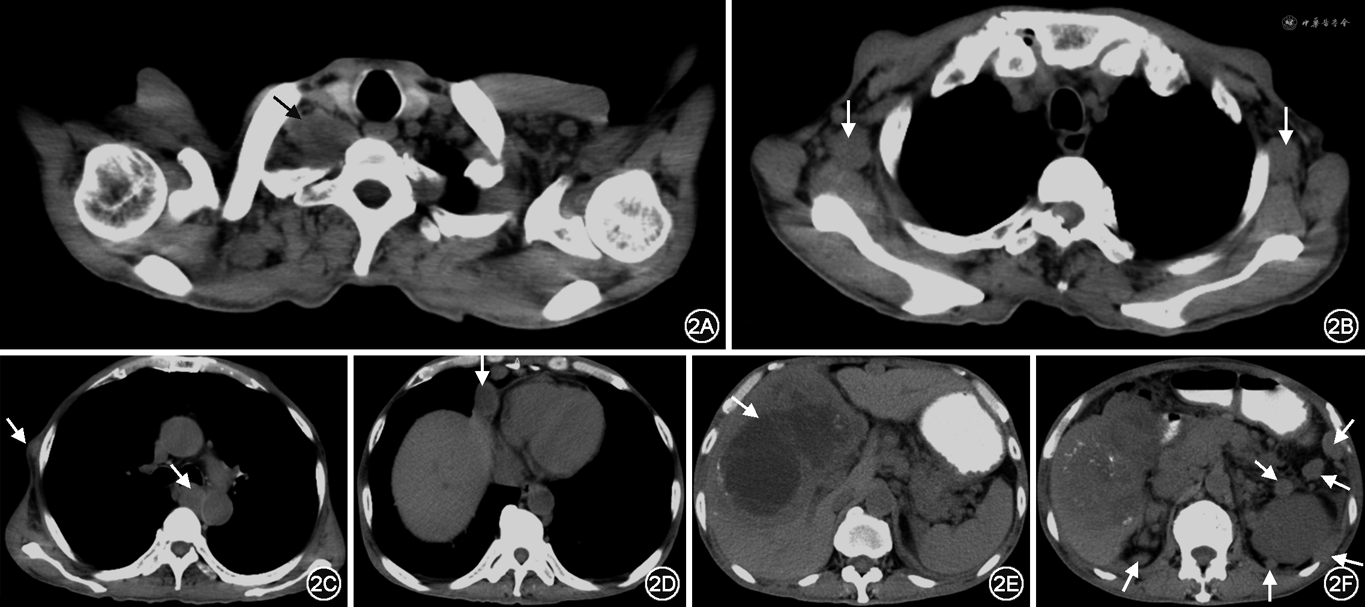

入院后完善相关检查,血常规未见明显异常。肝功能提示低蛋白血症及部分转氨酶升高:血清白蛋白 29.9 g/L,丙氨酸氨基转移酶 86 U/L,碱性磷酸酶 207 U/L,谷氨酰胺转肽酶 151 U/L,乳酸脱氢酶 268 U/L。肾功能结果正常。电解质提示轻度低钠血症:血钠 131.8 mmol/L。肿瘤标志物:癌胚抗原水平11.30 ng/ml,糖类抗原19-9水平27.18 U/ml。胸腹部CT提示:胆囊癌侵及肝脏伴有肝脏多发转移,腹腔、腹膜后多发肿大淋巴结,腹膜转移,腹壁转移,双腋窝、纵隔、右肺门及右侧颈根部多发淋巴结转移,左侧胸腔少量积液,少量腹水(图2)。

排除禁忌后行左侧头皮结节切除活检术及肝转移瘤穿刺活检。病理报告提示:左侧头皮转移性腺癌;肝脏穿刺组织低分化腺癌,倾向胆囊癌转移;免疫组化:CK8/18(+)、CK5/6(+)、p63(-)、CK7(-)、Glypican(-)、Hep(-)、MOC31(-)、CK20(-)、Ki-67(+约55%)(图3)。结合病史,明确诊断为胆囊癌(腺癌,cT4NxM1期,Ⅳ期),肝转移(多发),皮下转移(头皮、腹壁),淋巴结转移(腋窝、纵隔、颈部、腹腔及腹膜后),腹腔积液。确诊后给予止痛、营养支持治疗,腹腔穿刺引流腹水及腹腔灌注化疗,静脉给予吉西他滨化疗2个周期,疗效评价病情进展。调整治疗方案给予多西他赛联合顺铂静脉化疗1个周期,继续腹腔灌注治疗,但疗效欠佳。此后患者出现不全性肠梗阻、发热、口腔真菌感染等并发症,最终死于循环衰竭,从发病到死亡生存期共3个月。